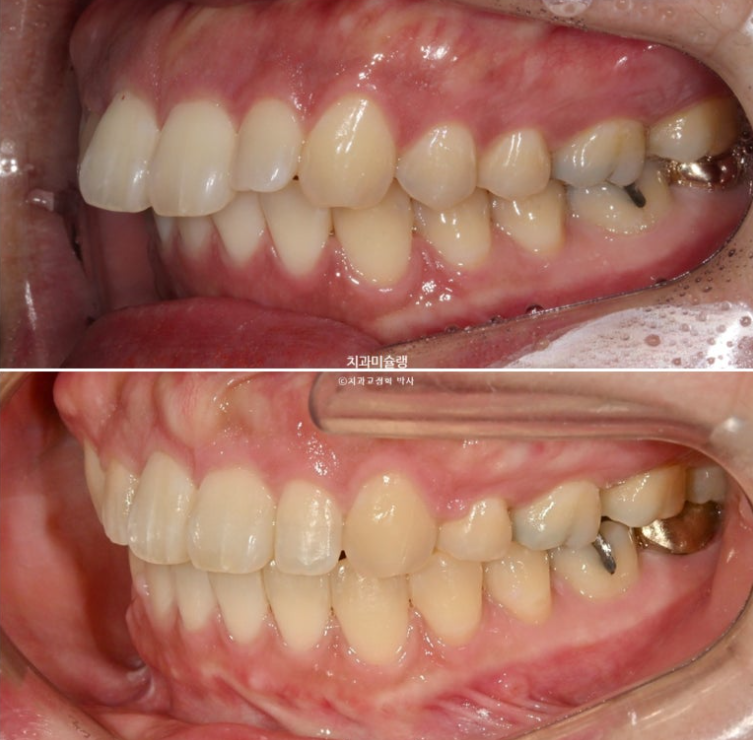

The midline and deep overbite have improved.

A stable, secure occlusal relationship is a given.

Let’s compare the before and after.

If you compare the before-and-after photos, you can see that the previously flat gum area above the front teeth has become uneven.

It is easy to misunderstand this as bone growing and protruding more than before, but in fact, the protruding part is the original position of the bone from before treatment, when the gums were protruding.

When the front teeth are successfully moved backward, including the roots, the gum bone covering the tooth roots also naturally resorbs and moves backward together with the roots. This is the process by which gum protrusion is resolved.

However, some areas of gum bone stubbornly remain in their original position and do not resorb.

As a result, these areas can look relatively protruded compared with the surrounding area after treatment, and this is the reason why the gums sometimes look uneven after extraction orthodontics.